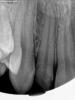

Гость razor Опубликовано 23 мая, 2011 Поделиться Опубликовано 23 мая, 2011 Коллеги, оцените, пожалуйста, снимки. Зуб 1.2.Использовал впервые вертикальную конденсацию, система Beefill, метод непрерывной волны. Беспокоит рентгенконтрастность, по сравнению с термафилом, и вообще, что можно сказать о качестве обтурации? Ссылка на комментарий

zybnaya feya Опубликовано 23 мая, 2011 Поделиться Опубликовано 23 мая, 2011 (изменено) Не поняла последнего снимка. Он что со спределром сделан? А так обтурация мне очень даже нравится. Без пор и паффов. У термафилов естественно конртастность выше будет,т.к носитель еще имеется. Изменено 23 мая, 2011 пользователем zybnaya feya Ссылка на комментарий